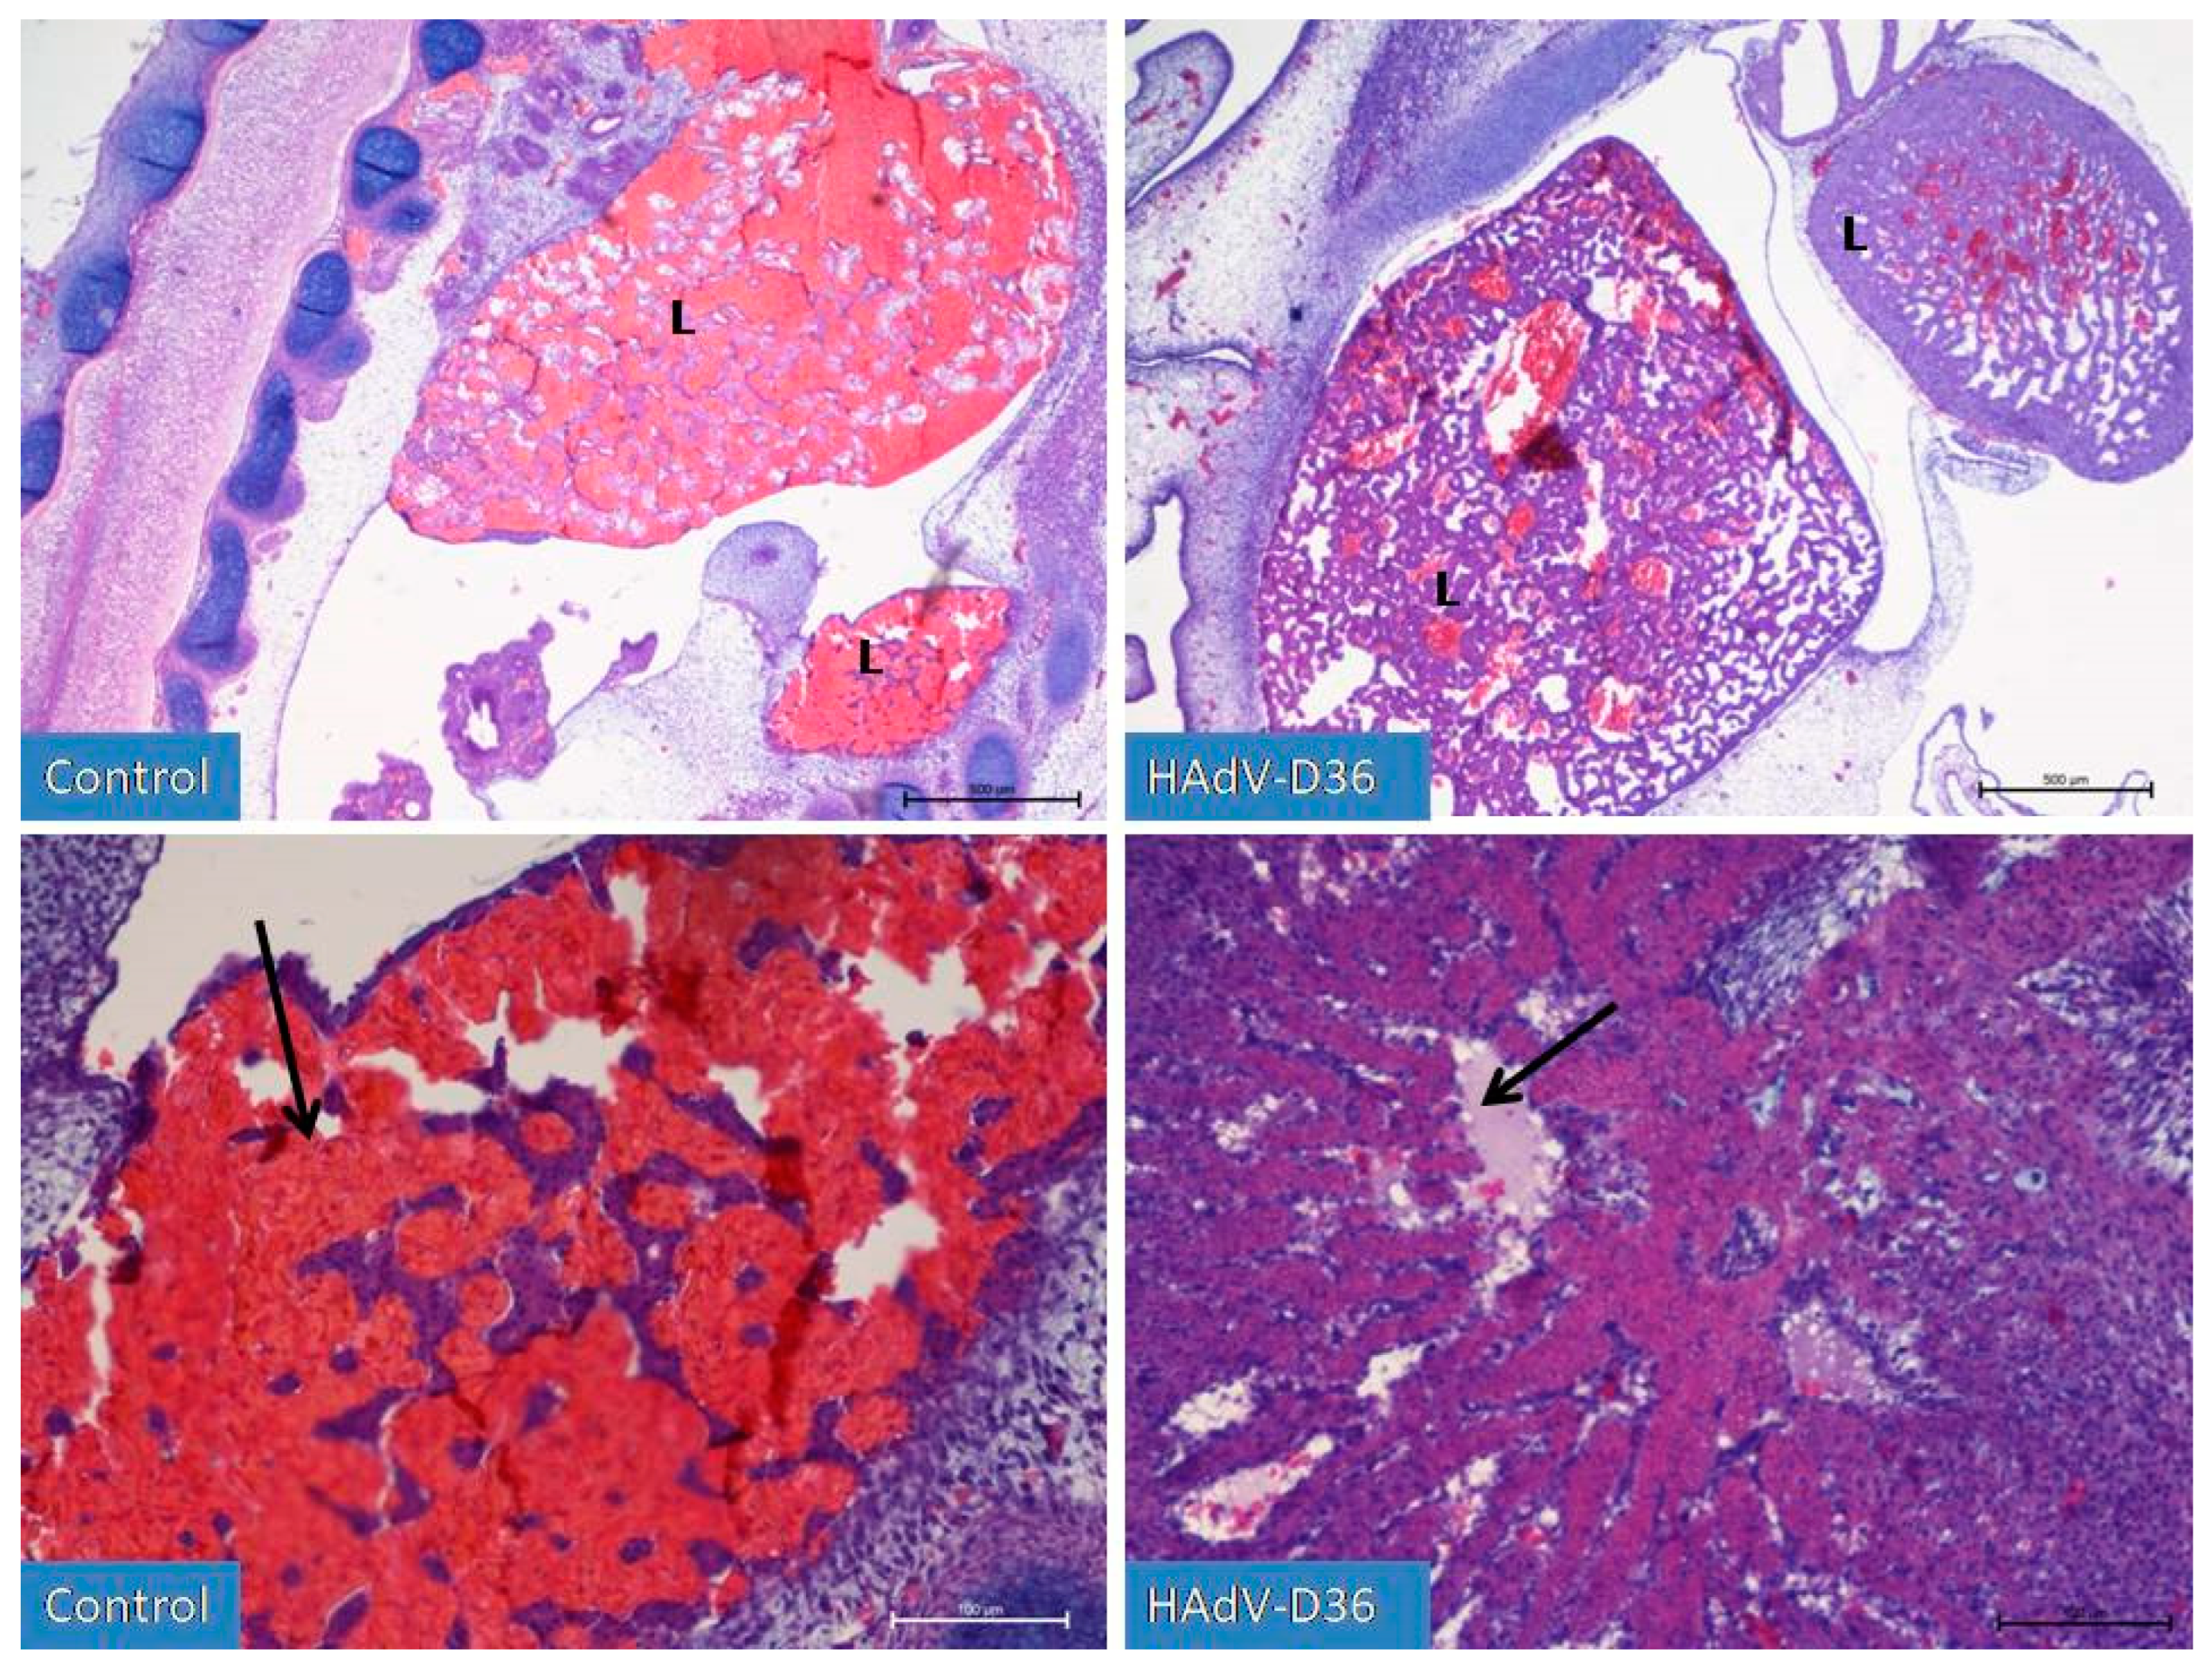

Figure 3. Liver development (L) on the 9th day of incubation of embryonated chicken eggs (ECEs) inoculated with human adenovirus 36 (HAdV-D36) or PBS (control) into the yolk sac. The liver of control ECEs is dominated by wide blood vessels filled with blood (black arrow). In the HAdV-D36-infected ECEs, hepatocytes comprise a significant part of the liver parenchyma, the blood vessels are much less filled with blood, and lymphatic vessels are clearly visible. H&E, Mag. 100, scale bar—500 μm (upper line) and 200×, scale bar—100 μm (lower line).

On day 8, HAdV-D36-infected embryos presented increased diameter of their vertebral cartilages, dorsal muscles, liver, and kidneys. After observing the embryos for the first 4 days, it was possible to conclude that the HAdV-D36-infected embryos’ development was about 2 days more advanced than the development of the control embryos. On the 9th day of development (Figure 3) in the HAdV-D36 group, it was possible to notice the initial stages of vertebral cartilage hypertrophy and calcification, the formation of joints in the limbs, or the initial phases of eye tissue organisation.

The liver and kidneys were enlarged and contained more parenchymal cells when compared to sinusoid vessels filled with blood.

No increase in the number of adipocytes in the chicken body was observed. On the 10th day of HAd-VD36 infection, we observed the initial phases of respiratory tract development, including clear formation of the lungs, which is unique for this stage of development of birds, as normally they begin to develop later. On the 13th day of the HAdV-D36-infected embryos’ development, we observed a glandular period in the developing lungs and the first drops of fat appearing in the liver. We observed a constantly increasing size of all organs, with particular emphasis on the liver and kidneys, which grew significantly faster every day until day 20 of embryo development. However, on day 15 (Figure 4), we observed the first inflammatory changes in the liver, which were followed by extensive lymphocyte–macrophage infiltration to the liver parenchyma and the vicinity of blood vessels in the following days. On days 19 and 20 (Figure 5), we observed substantial liver inflammation with the initial stages of a very pronounced liver lipidosis.